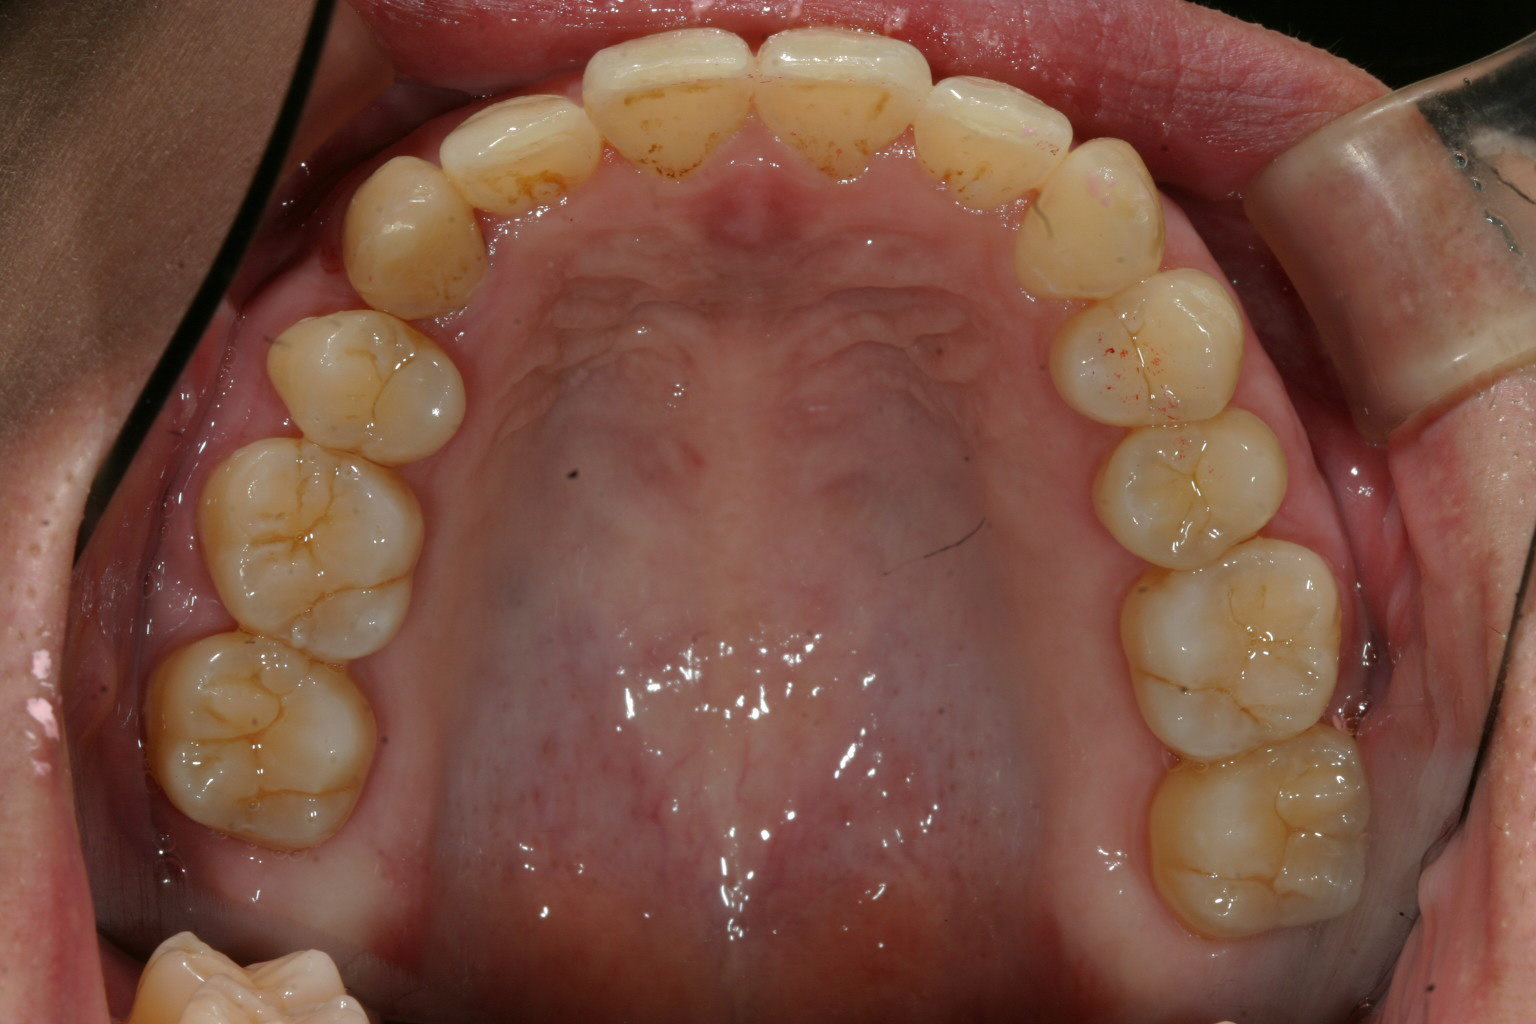

見てください、右上の小臼歯の有った場所に犬歯が移動してます。綺麗ですね~

前突感もバッチリです。